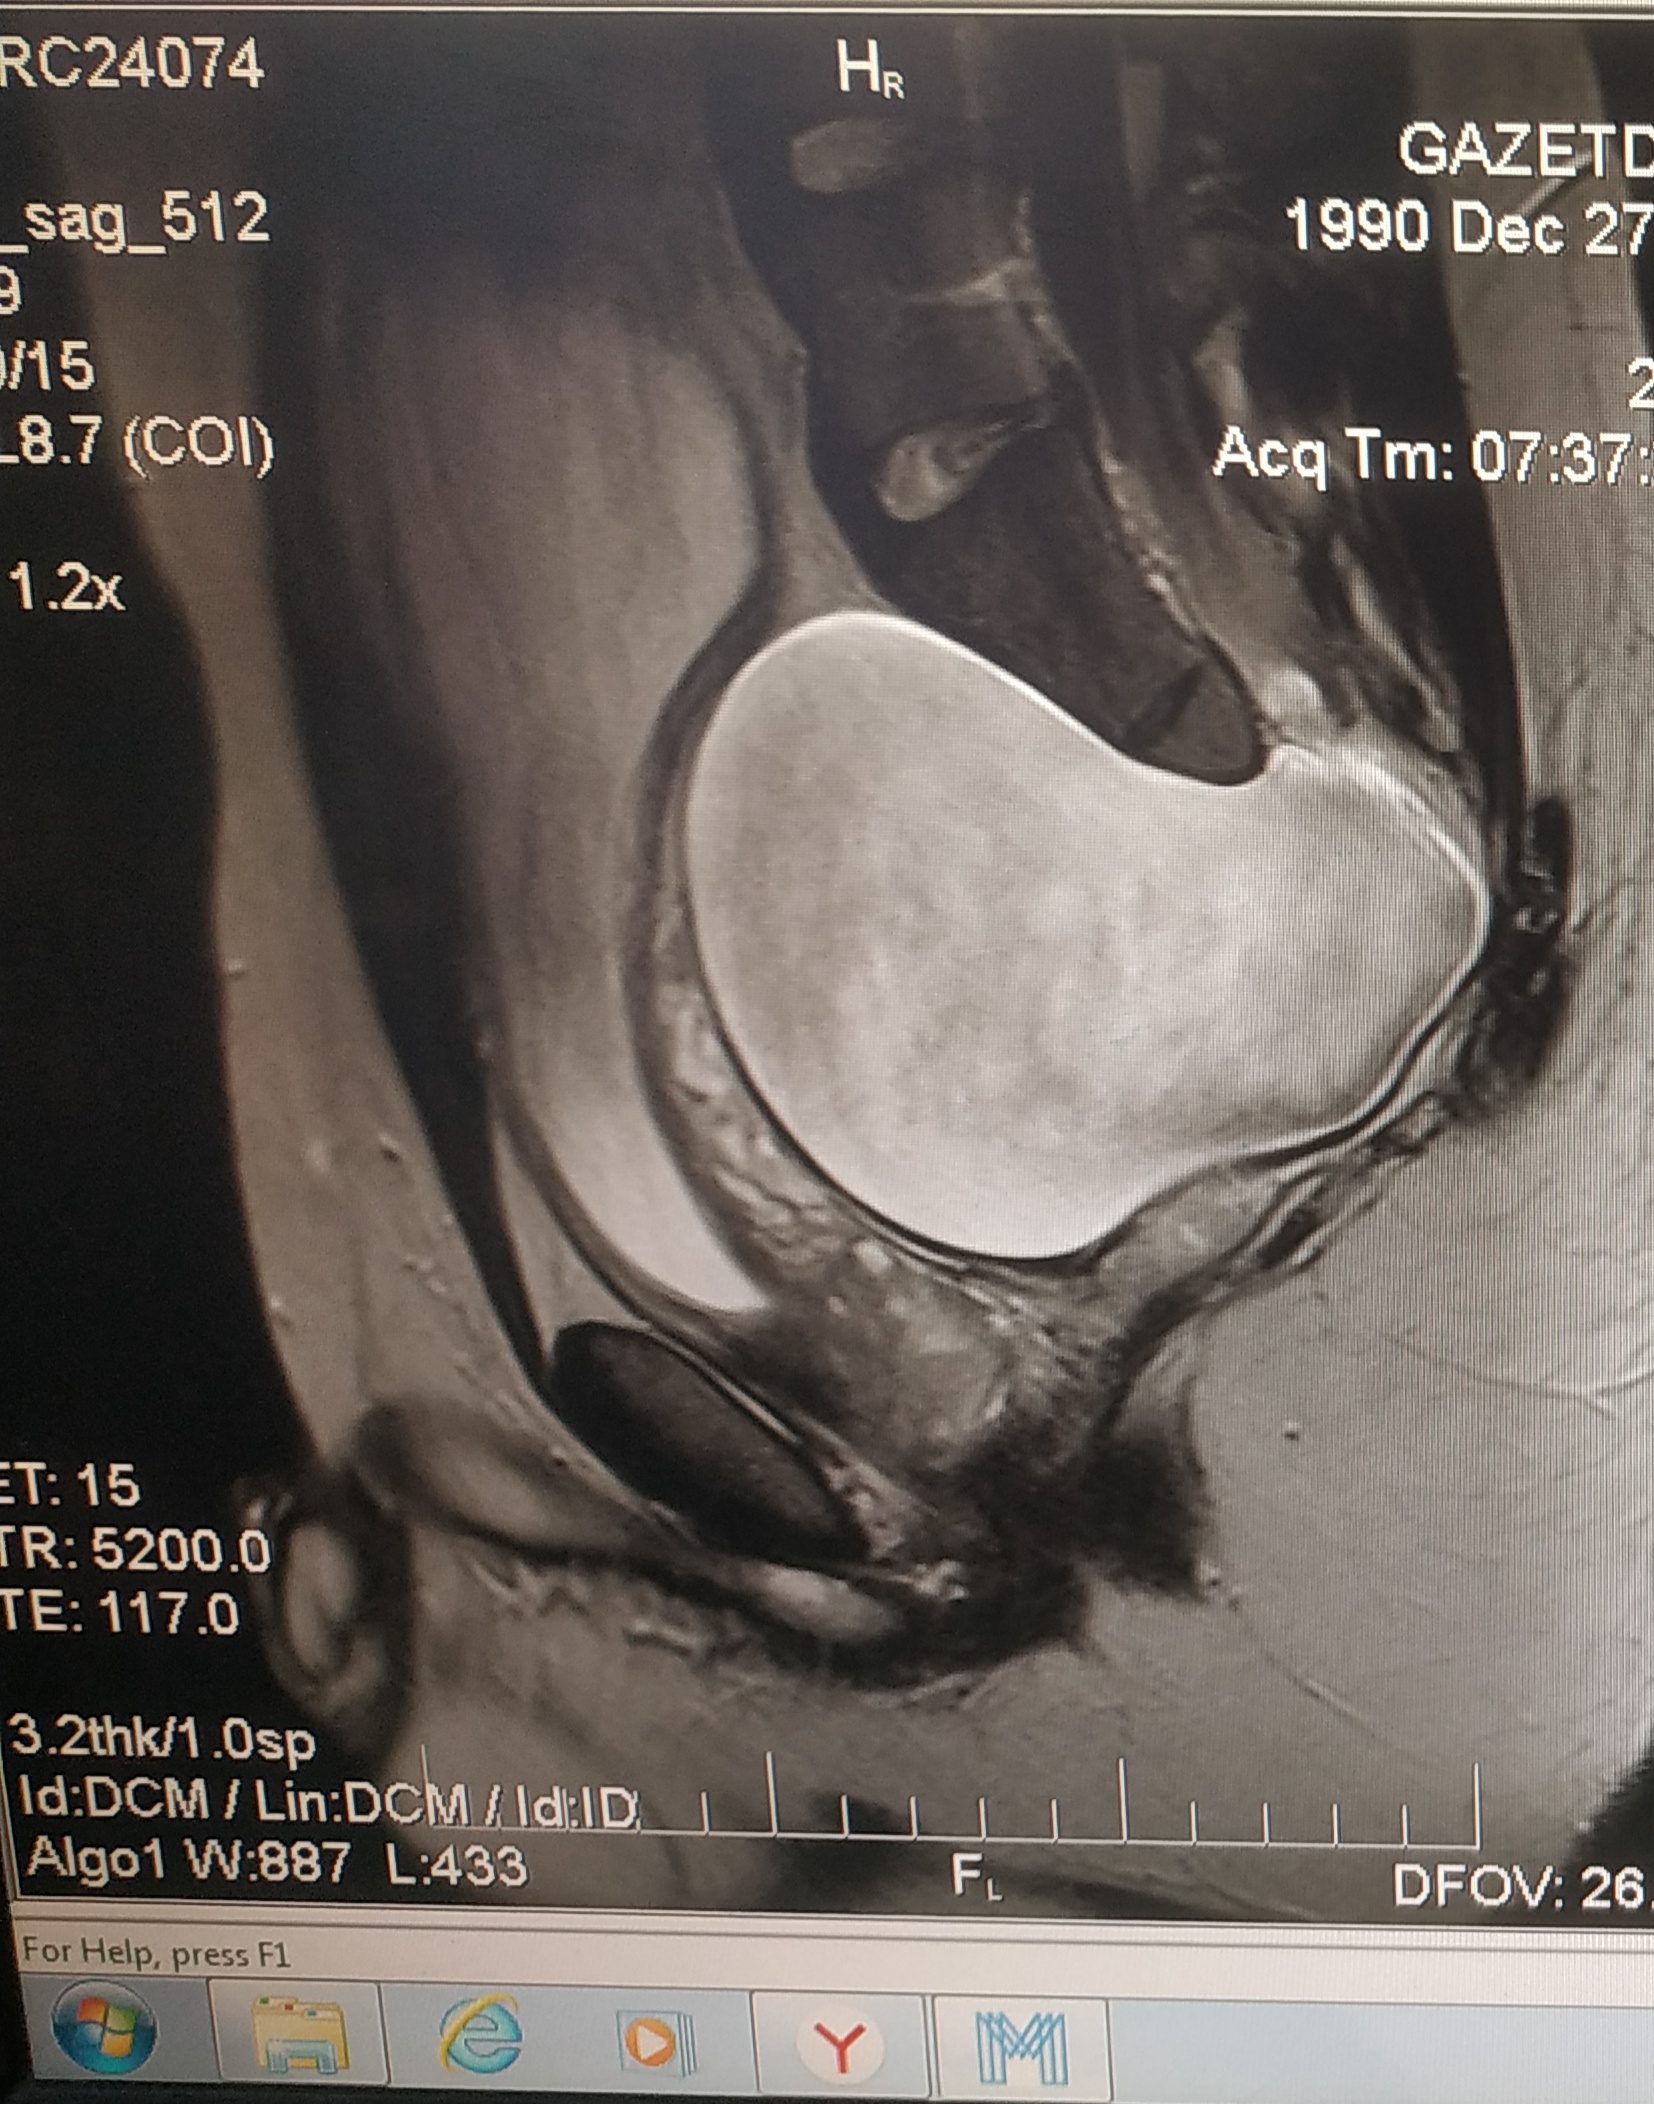

Здравствуйте! Скажите пожалуйста, оперировал ли кто нибудь из нейрохирургов в вашей клинике менингоцеле? Полный диагноз : менингоцеле крестцово - поясничного отдела s2-s5, Спинномозговая вентральная грыжа 11 см идущая в полость малого таза с компрессией мочевого пузыря, предстательной железы и дизурическими расстройствами. Мне 29 лет